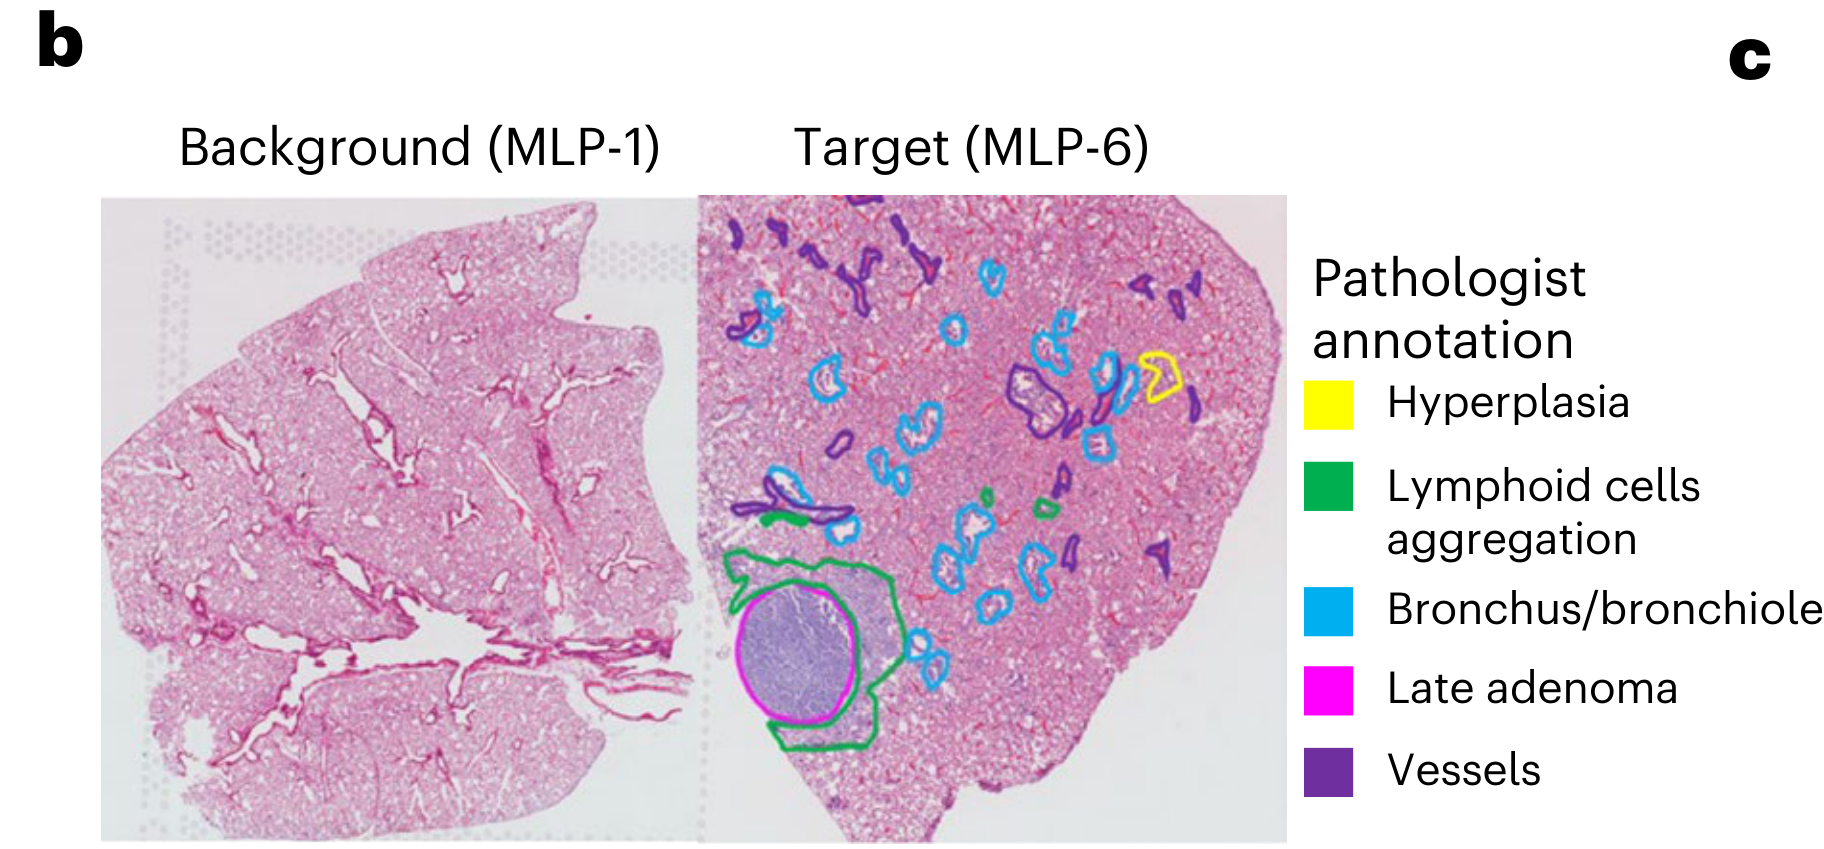

Jiang X. et al. - 2024

How are pathologist-defined tissue regions distributed across a cancer tissue section?

None (Item-level)